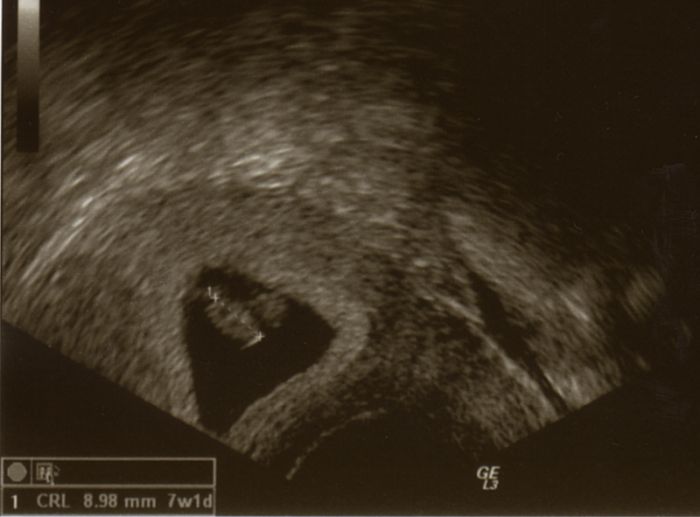

Ahoj, tak kontrolu mám za sebou a prý je vše OK! Hurá! A to, že nemám příznaky nic neznamená, nejspíš se dostaví později. Dokonce mi Dr. přidala 1 den, takže jsem dnes 7+1 a červík je prý pěkně živej. Vůbec jsem nečekala, že se mnou pohled na to srdíčko tak zacvičí. Děsnej doják

Gratuluji Mishi...krásný fotečka. Dojemné to je, to znám

[431292]Mish super fotečka a gratuluji,jen tak dáááál. Jsem moc ráda,že se nám všem daří